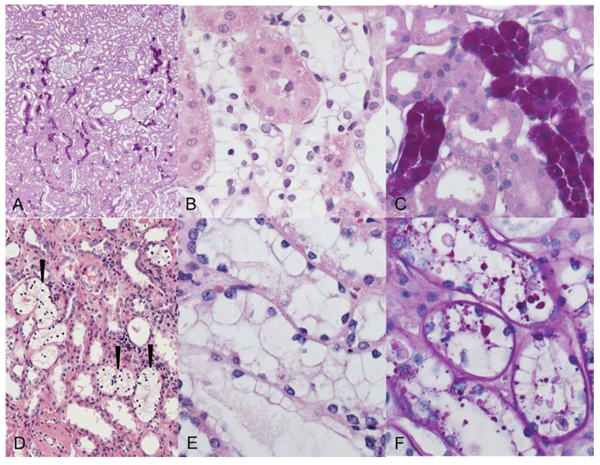

Figure 1: Clear cell tubules (CCT, A–C) of streptozotocin-induced diabetic rats and human glycogenotic alterations of distal tubules (D–F). A. Periodic acid-Schiff (PAS) reaction: distribution of PAS-positive rat AEL near the transition zone of renal cortex (upper part) and medulla (bottom). B. The cytoplasm of AEL cells is enlarged and appears clearly in hematoxylin and eosin (H & E) staining C. Magnification of PAS stain demonstrates the corresponding dense glycogen storage in distal AEL tubules. D, E. Human glycogenotic tubules (arrowheads) in a nephrectomy specimen. The similarity to rat CCT is easily recognizable in magnified H&E staining F. Glycogen is fast eluted in not perfused renal tissue, thus PAS staining is often patchy but still illustrates increased glycogen storage in enlarged tubules. Length of the lower edge A 1.25 mm, B, C, E, F 0.15 mm, D 0.5 mm.

CCT appear also as swollen tubulus epithelium with an “empty” looking cytoplasm in H&E staining, containing abundant glycogen, as demonstrated by the PAS reaction (Figure 1). Transition of distal tubule epithelial cells to glycogen storing CCT was evident. Furthermore, transformation of glycogenotic tubuli to small cell clusters or almost 1 mm large nodules occurred, thus representing advanced clear cell lesions. In rare cases, nodular lesions revealed a basophilic or acidophilic cytoplasm, enlargement of nuclei and prominent nucleoli, which can be interpreted as small adenomas (Figure 5).